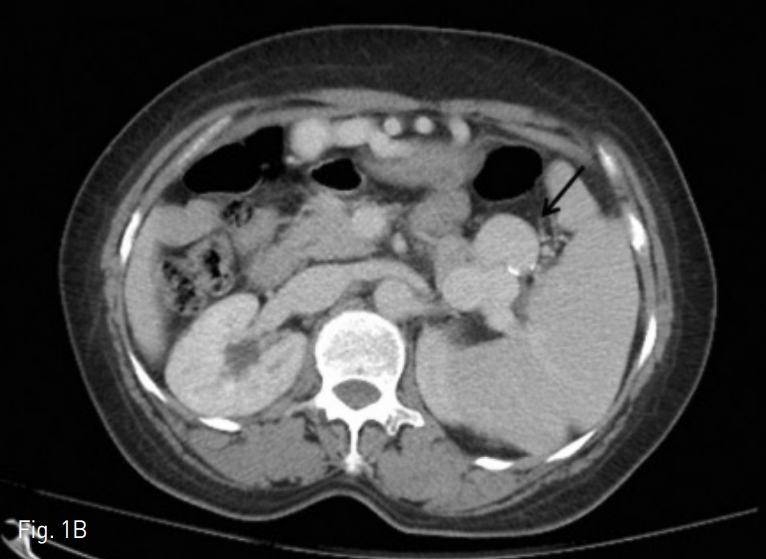

Fig. 1

A. A contrast enhanced axial CT image on arterial phase shows largest splenic artery aneurysm (arrow) with 4.5cm in diameter.

B. A contrast enhanced axial CT image on venous phase shows multiple splenic artery aneurysms (arrow) around splenic hilum.